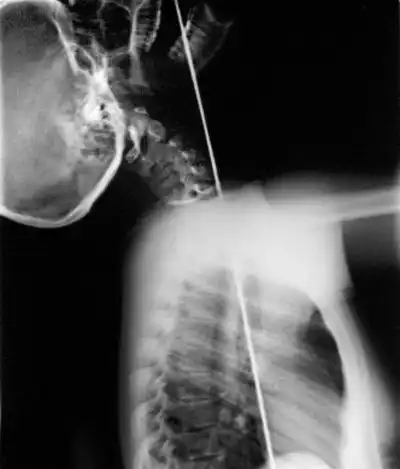

О человеке с так называемой военной выправкой и нарочито правильной осанкой злые языки скажут: он проглотил вертикальный несгибаемый предмет. Сразу представишь себе арматурный прут. И рентгеновский снимок военной выправки.

Такой:

После тренировок у шпагоглотателя притупляются ощущения в глотке и пищеводе. Циркач начинает учиться задирать голову так, чтобы глотка и пищевод уложились в прямую линию. Только при особенной, неповторимой осанке меч или шпага входит в пищевод, не касаясь чувствительных участков тракта, и даже в желудок фокусника.